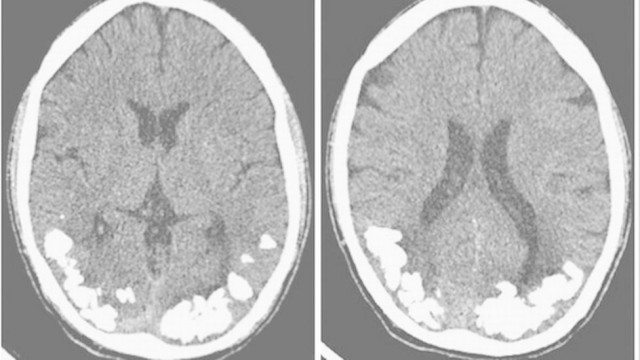

Um brasileiro de 49 anos, que sofreu a um acidente vascular cerebral, apresentou uma mudança de personalidade muito estranha após o incidente. De acordo com o relato do caso, publicado em agosto pela revista Neurocase, ele teria desenvolvido uma “generosidade patológica” e por isso, começou a distribuir dinheiro na rua e comprar doces para crianças alheias. Segundo sua esposa, ele tornou-se incapaz de administrar a vida financeira e estaria se endividando.

Aparentemente, o AVC que sofreu o deixou com uma “generosidade excessiva e persistente”. Os médicos chegaram a avaliar o paciente, mas não encontraram qualquer evidência de sintomas maníacos ou demência que pudessem explicar o caso. No entanto, uma tomografia computadorizada mostrou um baixo fluxo sanguíneo em várias regiões do cérebro, incluindo áreas no lobo frontal. Embora não estivessem danificadas pelo AVC, elas estão conectadas por caminhos neurais. Logo, danos nestes caminhos podem ter contribuído para a mudança de personalidade.